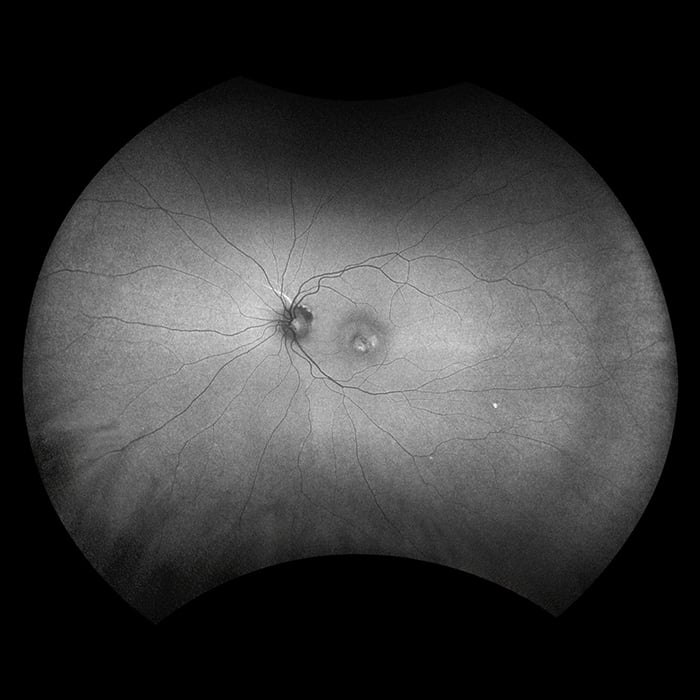

MonacoPro takes the proven Optos technology further by integrating cutting-edge MonacoPro SD-OCT image quality into every exam. Engineered for efficiency, MonacoPro captures up to five imaging modalities for both eyes in just 90 seconds, optimizing workflow, streamlining diagnostics, and delivering superior patient care.

The MonacoPro captures up to five imaging modalities for both eyes in just 90 seconds, optimizing workflow, streamlining diagnostics, and delivering superior patient care.

MonacoPro imaging modalities and image viewing options:

optomap Image Modalities

- color rg

- Sensory Retina

- Choroidal

- green af

- SD-OCT